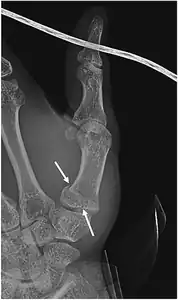

Bennett fracture

Bennett fracture on x-ray | |

A Bennett fracture is a type of broken finger involving the base of the thumb, which extends into the knuckle joint.[4][1] Symptoms generally include thumb swelling and pain.[1] Associated injuries may include ulnar collateral ligament injury of the thumb or trapezium fracture.[1]

The cause is generally a force along the long axis of the thumb.[1] Diagnosis is supported by X-rays.[1] There is nearly always some degree of disruption of the carpometacarpal joint.[2]